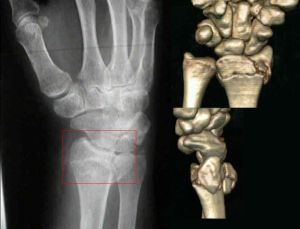

史密斯骨折1.關節外型:指骨折線不波及關節面者最為多見骨折線大多,呈橫形少數為斜形後者復位後維持對位較困難多需,附加手指牽引。

2.關節受累型:凡骨折線波及關節者均屬此型,由於史密斯骨折在臨床上少,見故無必要將此類患者再作更進一步的分型。

外傷使局部腫脹疼痛畸形骨折遠端向掌側移位腕,呈屈曲狀橈骨遠端向背側突出正側位腕關節X線片可明確診斷。

X線片上,典型的畸形是橈骨之遠折端連同腕骨向掌側移位,向近側移位。尺骨莖突可受累或不受累。很少有嵌入骨折,掌側骨皮質常有粉碎。